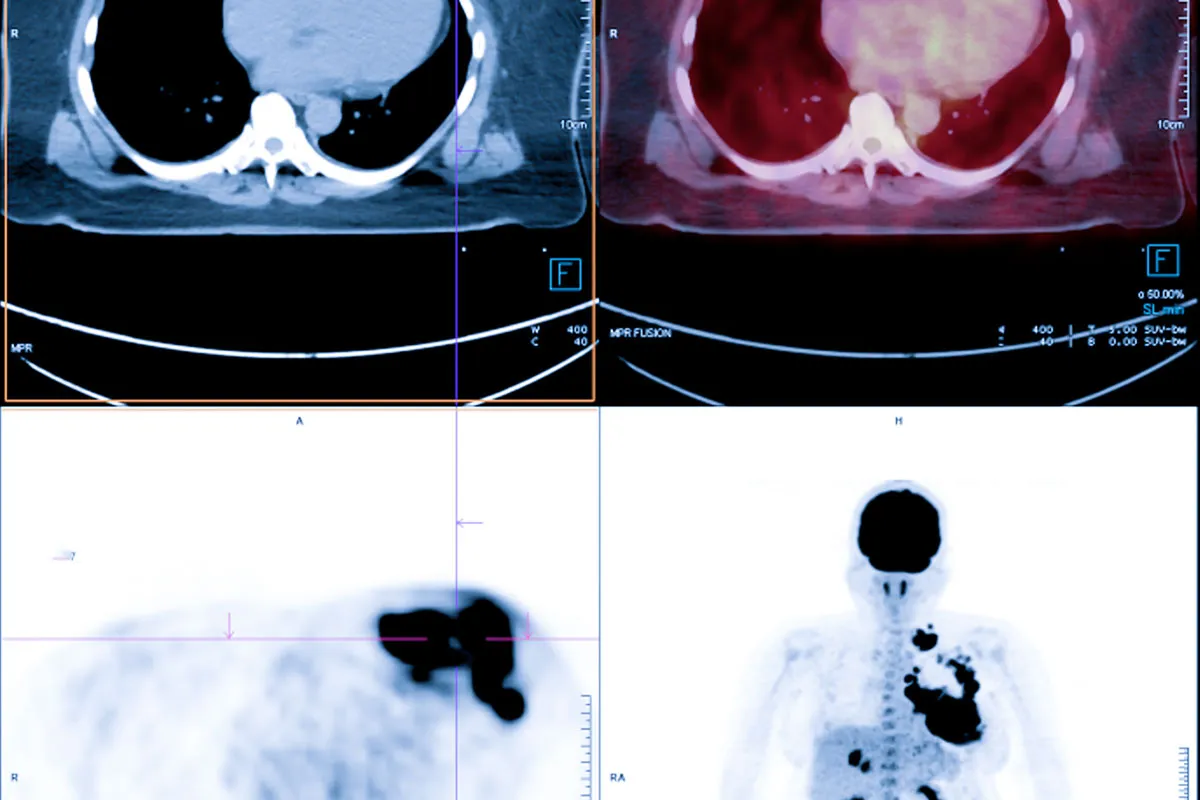

Изображения КТ-сканирования (Images of a Cat Scan)

Изображения, полученные при КТ-сканировании, играют ключевую роль. Они помогают врачам обнаруживать и лечить болезни.

Интерпретация КТ-изображений

Интерпретация КТ-изображений требует знания анатомии и патологии. Врачи-рентгенологи анализируют изображения, чтобы выявить аномалии, такие как опухоли, травмы или инфекции.

На изображении ниже показано, как КТ-сканер производит изображения внутренних структур:

В заключении, изображения КТ-сканирования являются мощным инструментом в медицинской диагностике. Они позволяют врачам получать детальную информацию о внутренних органах и тканях.

КТ в онкологии

В онкологии КТ-сканирование помогает обнаруживать опухоли. Оно показывает размер, форму и местоположение опухоли. Это важно для планирования лечения.